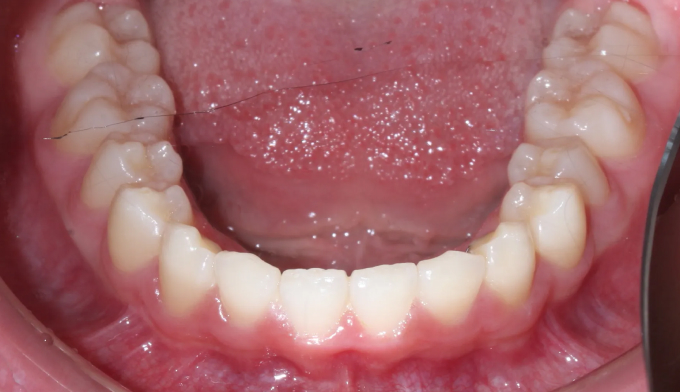

위 작은어금니가 겹쳐져서 맹출하였습니다.

공간이 부족하므로 먼저 양쪽으로 치아를 벌려 공간을 확보해준 후 겹쳐진 치아들을 배열해줍니다.

치아 배열 중 앞니가 뻐드러지지 않게 조심합니다.